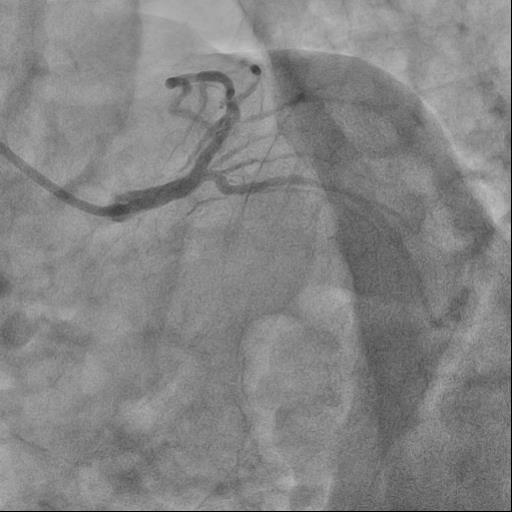

Angiography Right coronary artery dominance LEFT CORONARY ARTERY (LCA): trunk of the left coronary artery: uneven contours along the entire length. Left Anterior descending artery (LAD): uneven contours, stenosis in medial part by 80%. Circumflex artery (LCX): uneven contours along the entire length. RIGHT CORONARY ARTERY (RCA): uneven contours in the proximal segment, ¬³hronic total occlusion, the post-occlusionportion is fairly filled through intersystem collaterals.

The guide catheter was selectively placed at the RCA orifice, several attempts at antegrade recanalization were performed, after 10 minutes a decision was made to perform retrograde recanalization of the RCA, Sion Blue with the support of a Corsair 150cm microcatheter was successfully introduced through the septal branch into the middle segment of the RCA, escalation to Gaya 2 was performed and recanalization of the RCA was performed. Tip-In was performed in the antegrade guide catheter, the retrograde coronary guide was fixed with a balloon catheter. The retrograde microcatheter was advanced into the proximal segment, however, when performing Corsair, its defragmentation occurred, and the tip of the microcatheter itself was torn off. A decision was made to perform repeated recanalization of the RCA in a new lumen. Recanalization was successfully performed, then Tip-In was performed into the antegrade microcatheter and its successful passage beyond the occluded area. Balloon angioplasty and stenting of the RCA under OCT control with vFR.